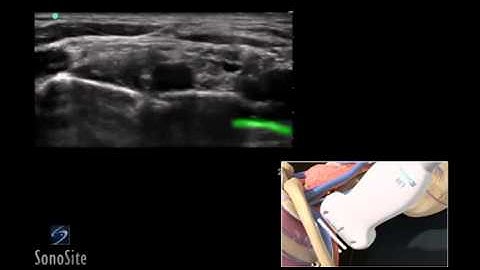

Ultrasound Guided Nerve Blocks